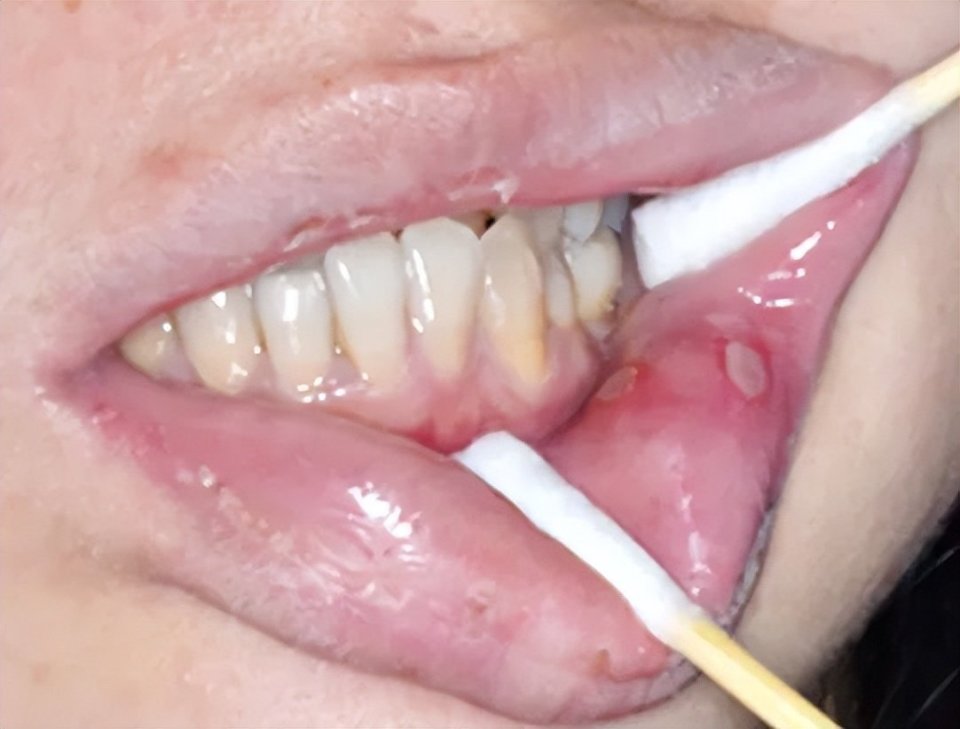

4、药物反应或创伤性溃疡

有明确的用药史或局部物理化学损伤史。

创伤性溃疡(图片源自陶人川教授团队)